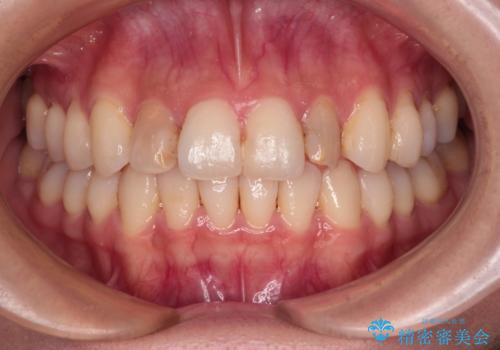

前歯をきれいにしたい オールセラミッククラウンにによる補綴